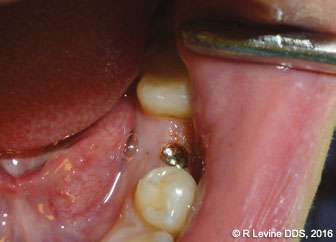

Figures 4A-4B, 5A-5B, 6A-6C, 7B-7C, and 8A demonstrate the enhanced hemostasis ensured by the LightScalpel CO2 laser. In Case 2, the patient had the vestibular extension procedure performed, and the hemorrhage was very well controlled, enabling the clinician with utmost precision. In Case 3, the bloodless excisional biopsy of fibroma was performed. Case 4 is a stage II implant uncovering procedure. This surgery requires both special accuracy and the well-controlled depth of laser energy penetration as well as enhanced hemostasis. No blood was present at any point. The implant was uncovered in approximately 30 seconds. In connection with implant uncovering, it should be mentioned that the recent study on the 10,600 nm CO2 laser removal of biofilm from titanium implant surfaces[11] reported that this laser wavelength does not affect titanium or titanium oxide (most common implant materials) and is therefore safe to use around implants. Case 5 shows a LightScalpel CO2 laser lingual frenectomy in a 7-year-old patient. Surgery is performed in a highly vascularized area where bleeding was well controlled. Finally, Case 6 is the ablation of the inflamed operculum. Figure 8A demonstrates the immediately postoperative view with excellent hemostasis.

Case 4: Stage II implant uncovering